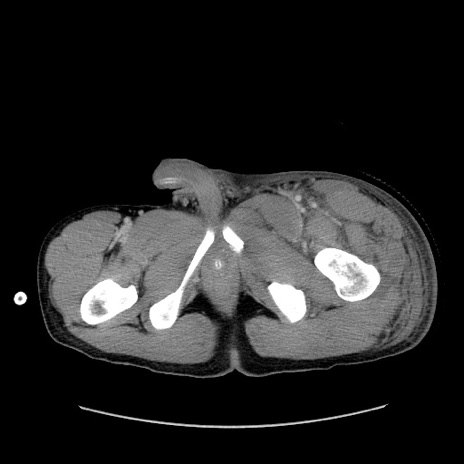

症例40 骨盤CT(横断像)

【症例】20歳代男性

【主訴】骨盤骨折

【現病歴】3日前にスノーボード中に木に衝突して受傷。遠方であり、当院紹介受診。

横断像